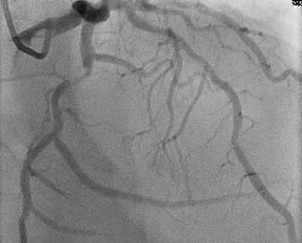

Patient was informed of these high-risk findings on CCTA with evidence of obstructive CAD and the decision was made to proceed with the gold standard left heart catheterization with coronary angiography to ensure accuracy of the obstructive lesion and intervention if the lesion was found to be obstructive. Cardiac catheterization revealed an obstructive lesion of the mid LCx with 80% calcified stenosis and he underwent successful Intravascular Ultrasound (IVUS) guided PCI of the LCx with pre and post balloon angioplasty utilizing a 3.5x22 and 3.0x15 mm overlapping Onyx frontier Drug-Eluting Stent (DES). LAD lesion angiographically appeared to be non-obstructive and medical management was elected (Figures 2-4).

Figure 4: Post PCI of the LCx revealing return of TIMI 3 flow.